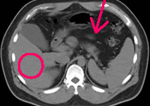

腹部CT

各臓器の形態がよくわかります。内臓脂肪の正確な計測もできます。

胆石

本人は右上腹部にときどき差し込むような痛みを自覚していた。

脂肪肝(○)と内臓脂肪の増加(矢印)

血液検査で中性脂肪が高く、腹囲が85cmを越えている。